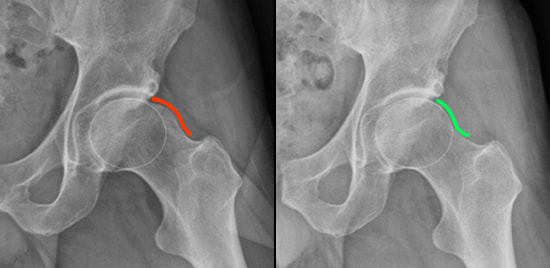

CAM Lesion Before & After Hip Arthroscopy

If these conservative treatments do not relieve pain, the condition is treated with an outpatient arthroscopic surgery to reshape the hip joint and prevent the impingement of the femoral head on the acetabular rim. Prior to the surgery, a low radiation CT scan is obtained to help plan the surgery. A 3D image is created from the scan and the rotational alignment of the socket and the thigh bone is calculated. This information helps guide the surgical plan. The outpatient surgery is done arthroscopically to minimize damage to the hip joint and muscles surrounding the hip. A burr is used reshape the ball and socket so they better match, and the labrum is reattached to the edge of the socket using bone anchors. This reshaping and/or repair work restores the proper anatomy of the hip, giving the patient the greatest chance of avoiding recurrence of symptoms – and may delay the onset of early arthritis or other related future hip problems.